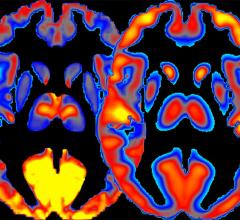

Nuclear imaging, also called molecular imaging, includes positron emission computed tomography (PET) and single photon emission computed tomography (SPECT) imaging. This section includes radiopharmaceuticals and tracers, PET-CT, SPECT-CT, and PET-MRI. Molecular imaging includes the field of nuclear medicine, which uses very small amounts of radioactive materials, or radiopharmaceuticals, to diagnose and treat disease.

May 13, 2022 — Alzheimer’s disease is the most common form of dementia, one of the major causes of dependency and ...

March 23, 2022 — A significant number of COVID-19 neurological complications— such as fatigue, headache, and cognitive ...